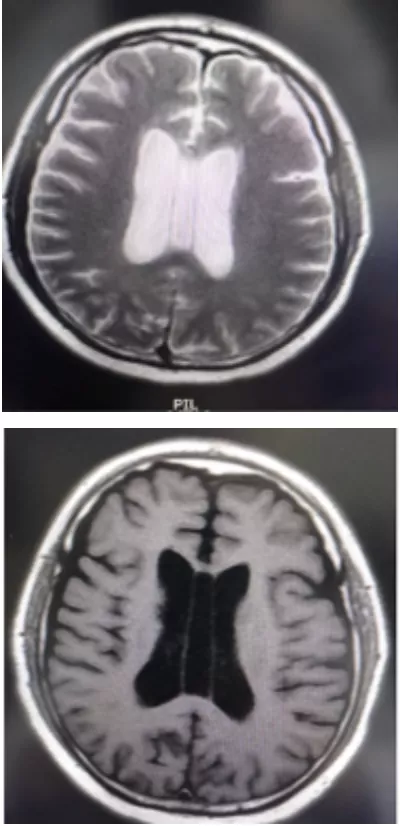

透明隔是兩側側腦室中間的間隔,在胎兒四個月時原始透明隔內形成一箇中縫,然後發展為分離的兩個小葉,兩小葉之間的間隙為透明隔間腔即CSP。腔的前上方為胼胝體,後下方為穹隆,側壁即透明隔小葉。正常情況下,此腔將逐漸融合而消失。如到一定年齡尚未融合且由腦脊液填充,即形成CSP,它在透明隔發育畸形時更加膨大。CSP不屬於腦室系統,因為它沒有後者所具有的室管膜。但是經常與側腦室或三腦室相通因為在氣腦造影時可積滿氣體,那些不與腦室系統相通者.腔內的腦脊液透過透明隔膜過濾和隔膜靜脈及毛細血管重吸收。

透明隔間腔是在顱內兩層透明隔之間形成的腔隙,它的上界為胼胝體體部,前下方為胼胝體膝部及嘴部和前聯合,底部和後方為穹窿。透明隔間腔被認為是人腦發育過程中的正常結構,通常在出生後的幾個月內閉合,但該結構亦存在於少數成人中。但是,將透明隔間腔稱為"第五腦室"是不正確的,因為它的內壁未襯有室管膜細胞,其內含有的液體也通常與腦室系統不同,因此透明隔間腔不具備腦室的組織結構特徵。

1.胼胝體膝部;2.透明隔腔;3.穹隆柱;4.穹隆體;5.穹隆腳;6. Vergae腔;7.胼胝體壓部